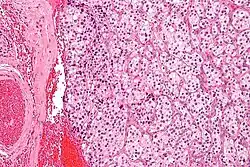

Makroskopisch sind sie vorwiegend rund-ovale, rotbraune bekapselte Gebilde, die gelegentlich den Knochen infiltrieren. Histopathologisch bestehen sie aus Zellballen, die von einem feinen kapillaren Netzwerk umgeben sind. Immunhistochemisch enthalten die Zellen Chromogranin A und Synaptophysin. Um die Zellballen liegen teilweise sogenannte Sustentakularzellen, die S100-Protein enthalten.